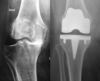

Prothèse de genou

Prothèse totale de genou de première intention : c’est l’implantation d’une prothèse totale de genou sur une articulation vierge de toute chirurgie antérieure. Elle remplace la totalité du genou c’est-à-dire les surfaces articulaires situées entre le fémur et le tibia mais aussi entre le fémur et la rotule.